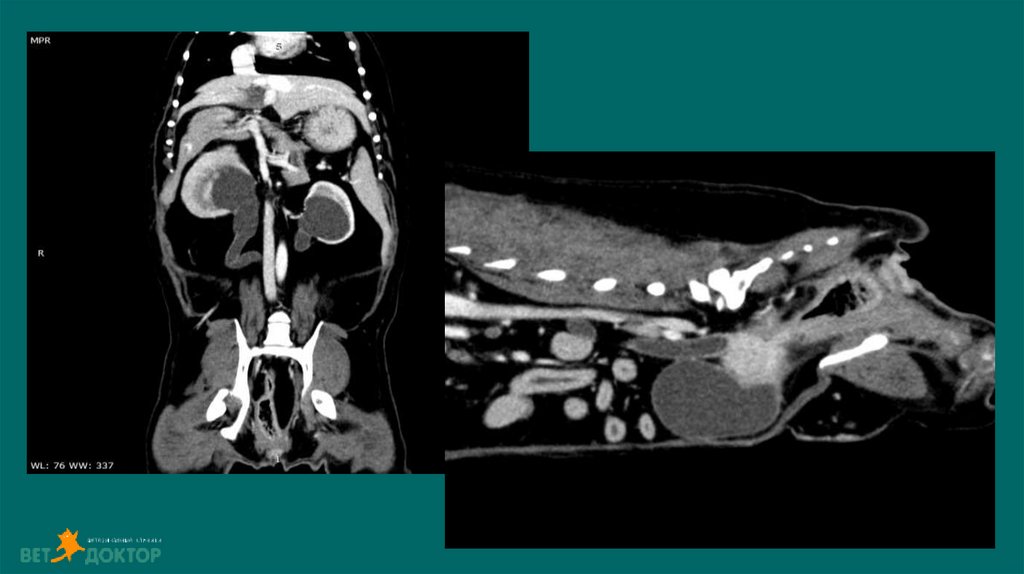

КТ

«Затеки» свободной жидкости в брюшной полости(подозрение) Выход контраста за

пределы мочевого тракта(подтверждение)

36. Уретеролитиаз-гидронефроз

Диагноз: УЗИ. Рентген. Пиелография. КТ(урография)